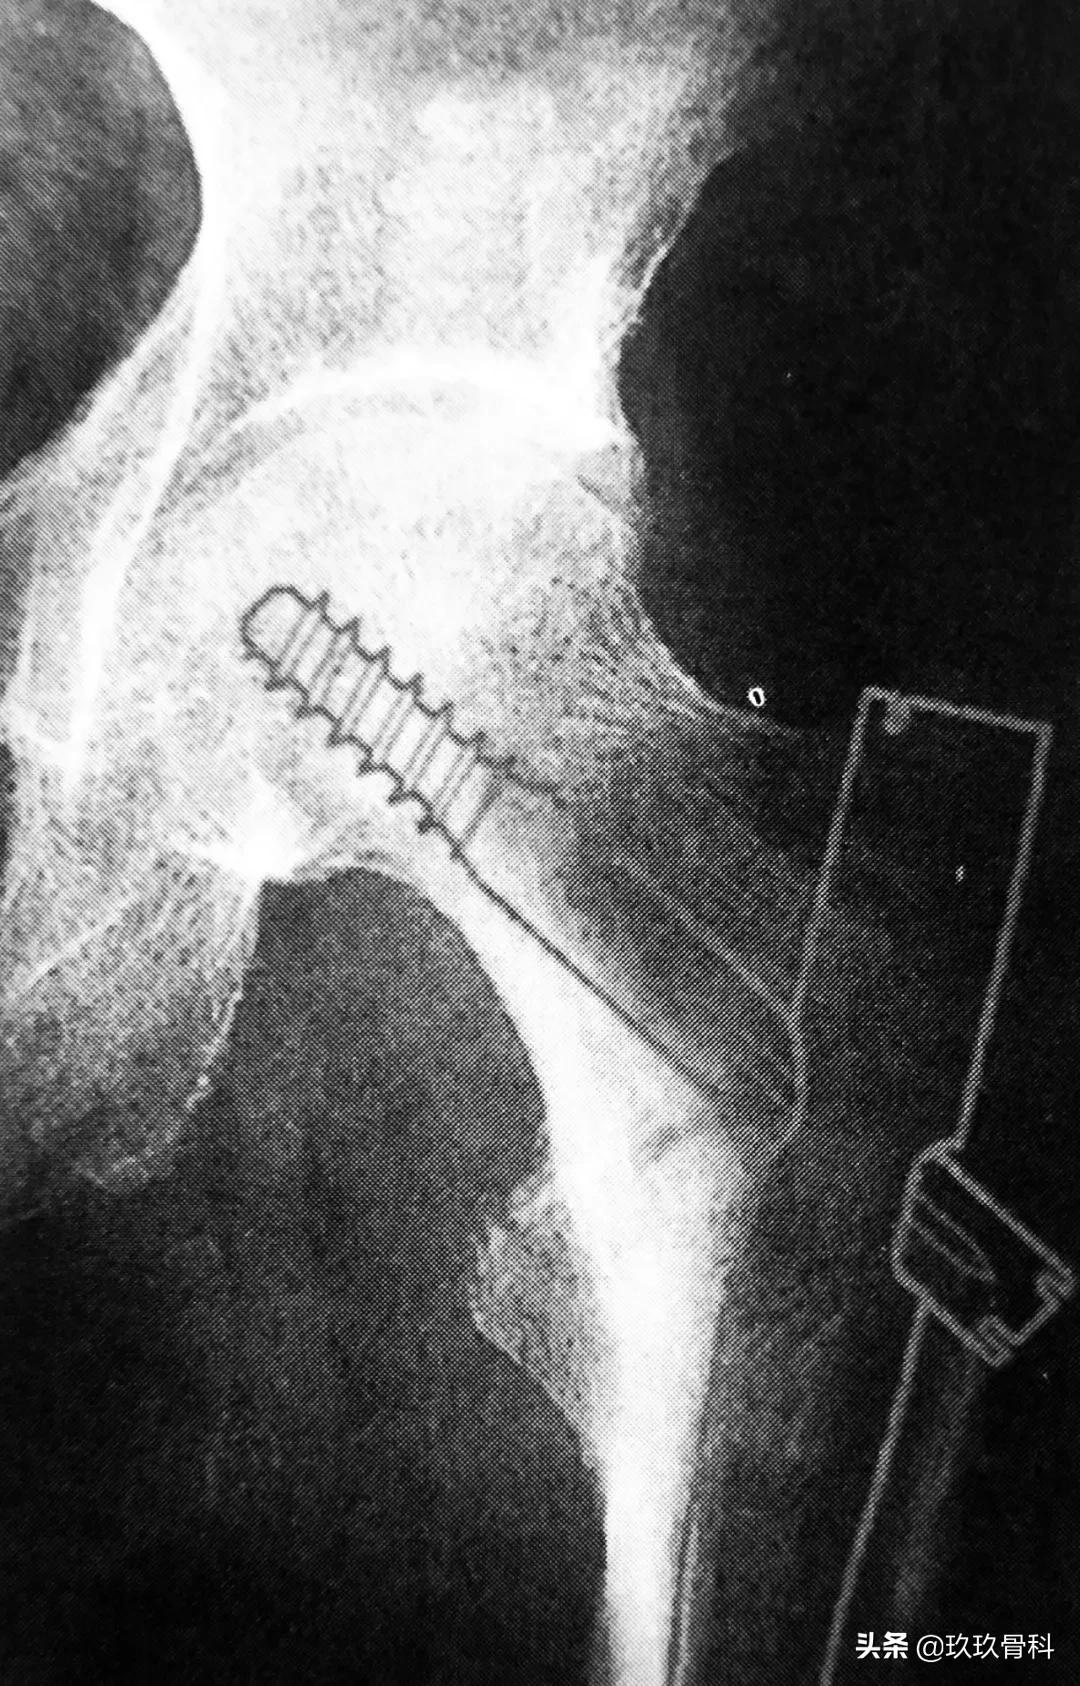

骨科取髓内钉的视频,骨科髓内钉内固定术式简写

术前 Gamma 钉的选择

术前必须仔细确认所用 Gamma 钉和拉力螺钉的角度,在 X 线透视下观察确认颈干角,以达到最佳固定效果。确定 Gamma 钉及配套器械后,切开皮肤前先预装配,以检查各孔道是否配套准确,连接处是否牢固。

A 拉力螺钉的安装;B 拉力螺钉的正确位置